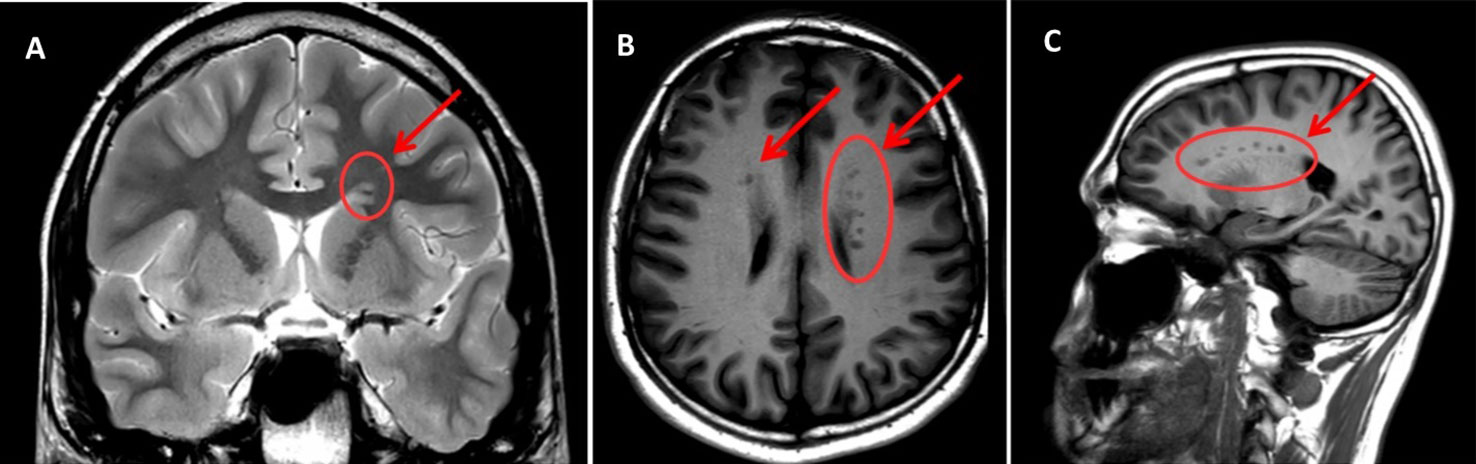

cavernoma

dilated vascular cavity lined by vascular endothelium

typically supratentorial

popcorn appearance on MRI, core can be hyperintense, dark rim on T2

can cause seizures, can bleed